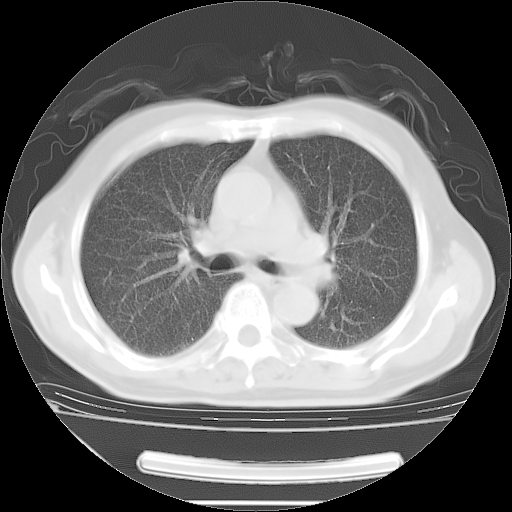

今天复查肺部CT,发现双肺广泛磨玻璃样改变。所以我把3月19日和5月9日相隔50天的肺部CT上传。请大家会诊。

5月9日肺部CT(在4月27日齐鲁医院肺部CT描述部分肺组织磨玻璃样改变,12天后肺组织广泛磨玻璃样改变)

2009年5月9日肺部CT